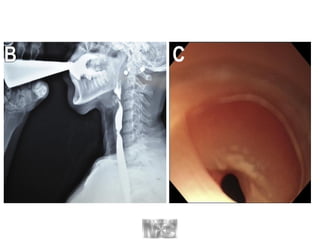

DIAGNOSTICO

• Esofagograma con bario

• Manometria esofagica

• Esofago en

“Sacacorchos”